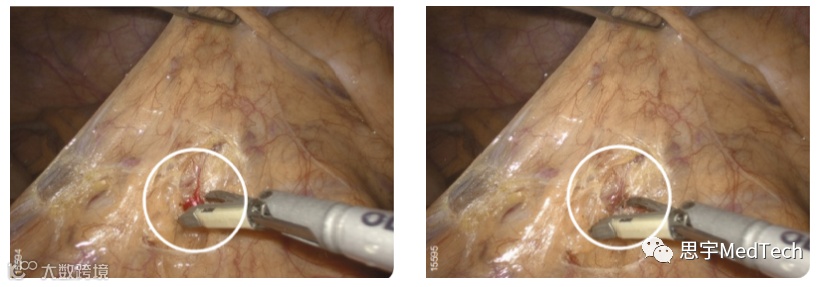

▲对7mm血管实现渗出性出血的控制(图片来自官网)